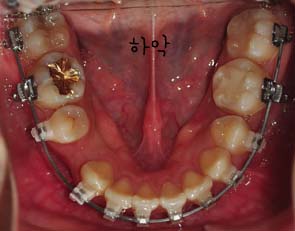

저는 스크류 2개를 입천장에 심어서 이것을 킬본교정장치와 연결아서 당김으로써 앞니가 들어가는것에 효과를 주도록 하였는데요

스크류를 정확히 어느 부위에 심은것이냐고 여쭈니 잇몸뼈라고 하시더라구요

사진과 같이 보시면 입천장에 스크류가 심어졌을때의 모습이 보이시나요? 사진과 같이 두개의 스큐르를 심은후 고무로된 연결고리로 연결하여 킬본교정장치에 걸어서 당기고 당기고~ 를 해주는겁니다 *,*